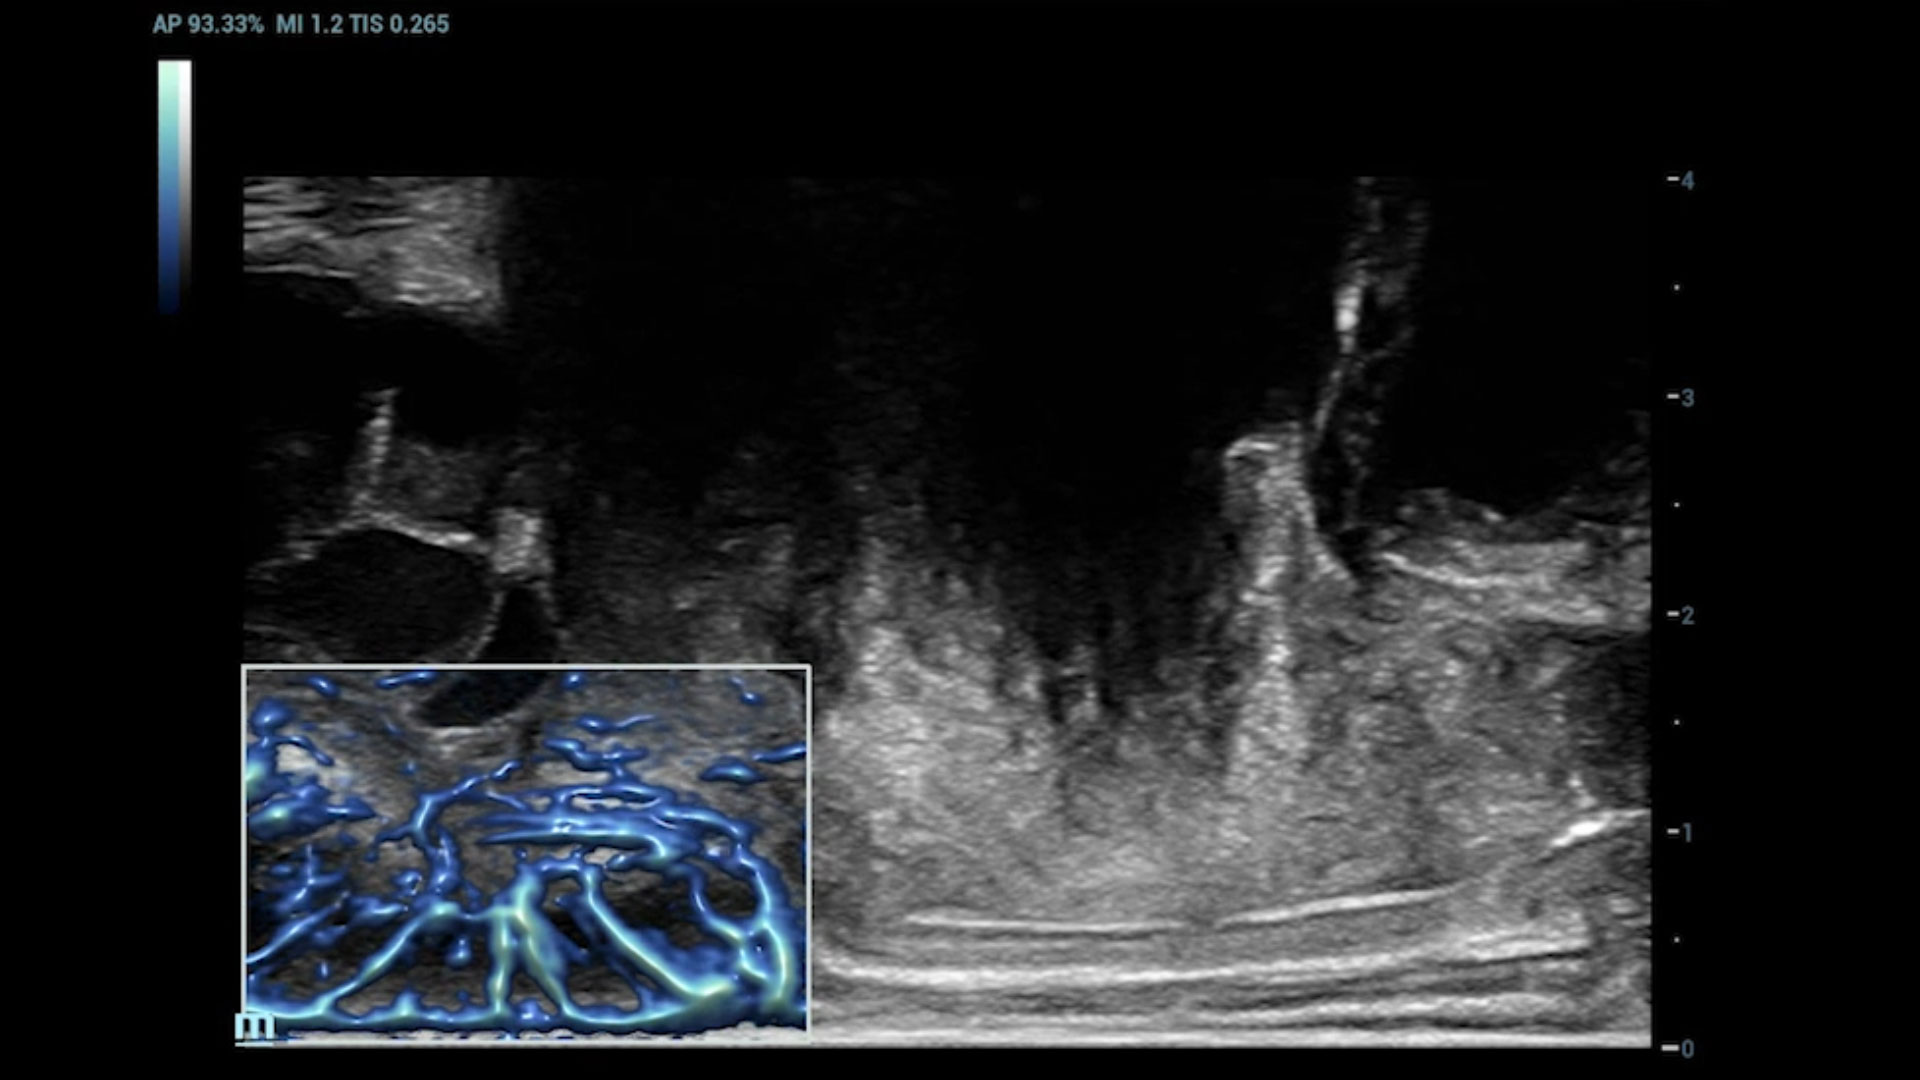

UMA (Ultra-Micro Angiography)

The innovative technology breaks the bottlenecks of traditional Doppler imaging. With ultra-high spatial resolution and flow sensitivity, it allows detecting super-subtle and super-slow flow perfusions, thereby extending the clinical application of qualitative and quantitative ultrasound evaluation in fetal brain, kidney, placenta, endometrium, ovary, etc.

3D UMA - fetus intracranial flow